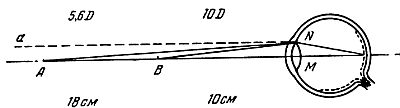

Если отчетливое изображение точки на сетчатой оболочке глаза получается при ее удалении на расстояние не более 35 см — глаз страдает легкой близорукостью, от 35 до 10 см — средняя степень и если наибольшее расстояние отчетливого видения не превышает 10 см — сильная степень близорукости. Согласно рис. 4 степень близорукости определяется тем углом, который образуется между лучом aN, идущим из бесконечности, и лучом, идущим из дальней точки А, т. е. углом aNA или, что то же, NAM.

Рис. 4. Близорукий глаз. Изображение предмета получается перед сетчаткой.

Мера аккомодации определяется разностью углов NBM и NAM при дальней и ближней точке. Например, положим, что для какого-либо близорукого глаза дальняя точка отстоит от глаза на 180 мм, а ближняя на 100 мм.

В таком случае степень близорукости выражается углом 1/180 = 0,0056, т. е. 5,6 D (диоптрий).[6] Мера аккомодации выражается разностью углов 1/100— 1/180 = 4/900 =0,0044, т. е. 4,4 D.

Близорукий глаз имеет главный фокус преломляющей системы перед сетчаткой. Если рассматриваемый предмет приближается к глазу, то приближается к сетчатке и его изображение. В случае близорукости или ось глаза слишком длинна, или кривизна хрусталика велика, или преломляющая способность других сред глаза велика.

Близорукость исправляется очками с вогнутыми стеклами.